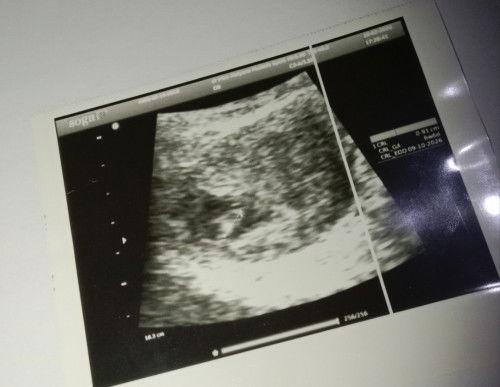

Bun ini gimana ya kata dokternya belum keliatan apa" disuruh usg lgi 3mnggu, hpht 23des

Udah coba usg transvaginal, bun? Bisa jadi usia kehamilannya masih kurang buat dideteksi sama alat usg. Tapi kalo berdasarkan hpht, biasanya udah mulai kelihatan. Tunggu dulu aja sesuai yang dokter sarankan, bun. Selama nunggu, bundanya jangan kecapean. Semoga membantu.

sama bun HPHT nya, 8week masih kantung belum ada janin